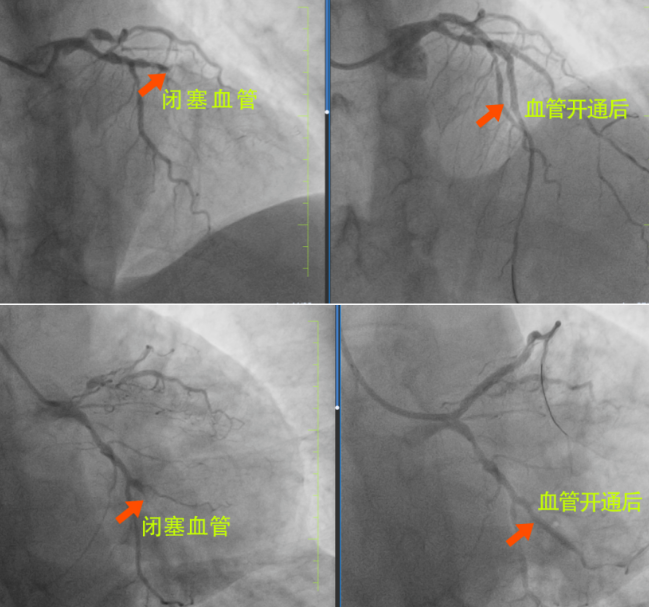

很快,長(zhǎng)春國(guó)文醫(yī)院心內(nèi)科為患者安排了手術(shù),為患者進(jìn)行手術(shù)的是長(zhǎng)春國(guó)文醫(yī)院副院長(zhǎng)、心血管中心主任隋立有。隋院長(zhǎng)在心血管領(lǐng)域造詣深厚,擁有豐富的臨床經(jīng)驗(yàn)。隋院長(zhǎng)始終專注于心血管疾病的研究與治療,對(duì)各類復(fù)雜心血管病例有著獨(dú)到的見解和精準(zhǔn)的判斷。隋院長(zhǎng)在了解患者的病情后,迅速制定了治療方案。患者3根血管完全閉塞,情況十分危急。但隋院長(zhǎng)憑借著精湛的醫(yī)術(shù)和豐富的經(jīng)驗(yàn),巧妙地開通了2根血管,整個(gè)手術(shù)過程僅僅用了不到半小時(shí),就成功完成了3枚支架的植入。這一高效且精準(zhǔn)的手術(shù),讓患者和家屬驚嘆不已,也讓他們真切地感受到了國(guó)文醫(yī)院心內(nèi)科雄厚的師資力量和成熟的技術(shù)實(shí)力。